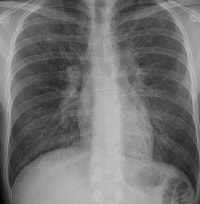

リウマチでは、

間質性肺炎、

肺線維症がみられることがあり、これらはリウマトイド肺とよばれています。自覚症状としては、息切れ、空咳などがあります。ただ、メトトレキサートをはじめとする抗リウマチ薬の副作用でも間質性肺炎をおこすことがありますので、どちらの原因でおこったのかを見極めることが、治療上大変重要になります。

肺に水がたまる胸膜炎をおこすこともあります。さらに、まれですが、 閉塞性器質性細気管 支肺炎(BOOP)といわれる移動性の肺炎をおこすこともあります。